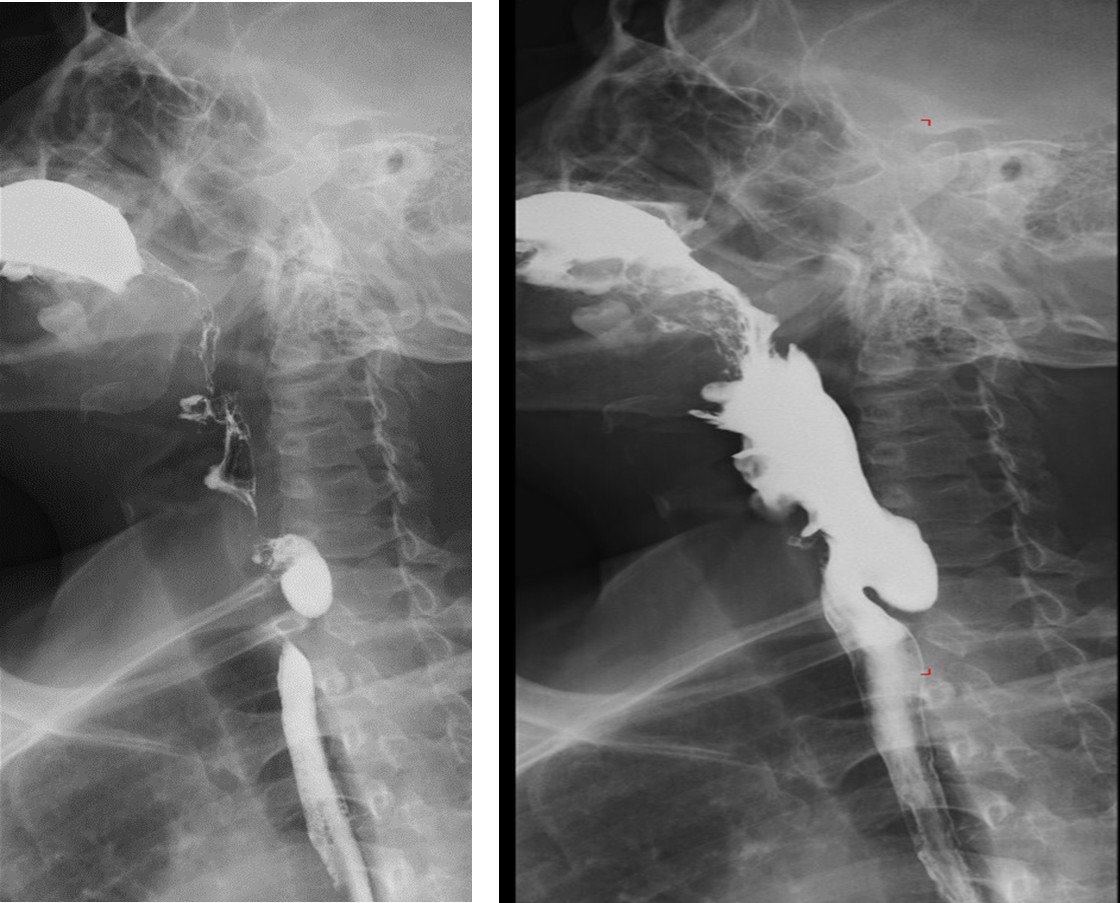

Esophagram: Residual Zenker's diverticulum, although marsupialized.